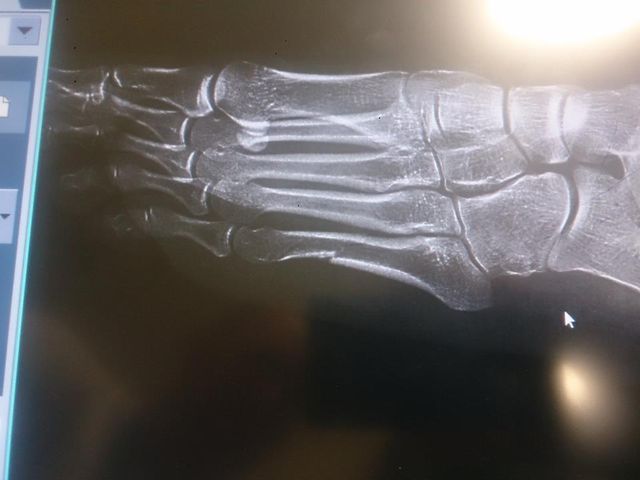

Zawodniczka najwyraźniej poirytowana poradami “ekspertów” wrzuciła na Facebooku rentgen swojej stopy.

Prześwietlenie mojej stopy. Wielowarstwowe złamanie. Z pozdrowieniem dla wszystkich “ekspertów” :)) Spokojnie, biegam dalej

– napisała Kowalczyk.